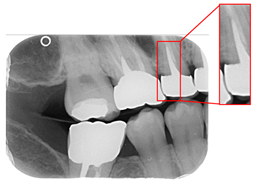

Caries are a prevalent issue in dental healthcare, affecting nearly all adults and 60–90% of children, posing a significant public health challenge, especially with dental braces or dental restorations [,]. Traditional dental examinations relying on visual inspection or radiographic images [,] can be subjective and time-consuming. Related studies have utilized auxiliary software for oral examinations, such as methods of geometric alignment to compare noise levels in subtraction images [], jawbone regeneration [], and corticalization measurement []. With the rise of AI, automated caries detection using image processing and deep learning technologies has gained increasing attention []. Deep learning techniques such as convolutional neural networks (CNNs) have shown significant performance in medical image classification by leveraging large-scale annotated datasets [,]. In dentistry, CNNs have been applied to detect apical lesions, offering objective interpretation and reducing diagnostic time []. Bitewing radiographs (BWs) are commonly used to identify caries and periodontal conditions. Tooth region extraction from BWs can be performed using filtering, binarization, and projection methods [,,,]. The YOLO object detection algorithm enables real-time localization with high accuracy and speed [,]. This study uses YOLO to detect caries under restorations and dental braces, as illustrated in Figure 1.

Figure 1.

BW images with disease. (a) Dental braces. (b) The red circle represents the restoration. (c) The gap in the red circle indicates dental caries under the restoration.